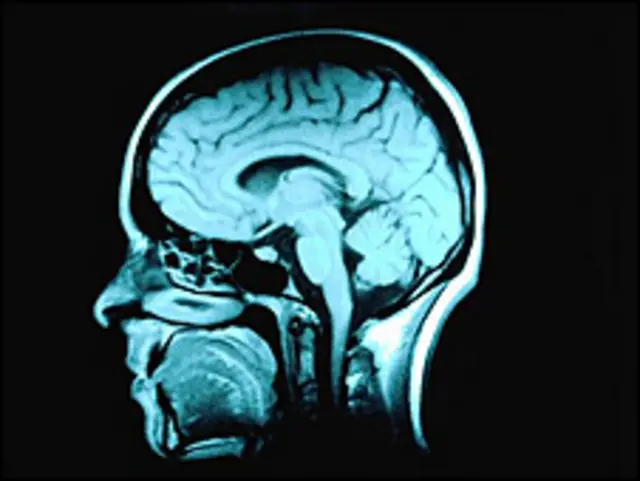

En el estudio se utilizó un escáner de imágenes de resonancia magnética funcional, que puede medir los niveles de activación en diferentes partes del cerebro al detectar un aumento en el flujo sanguíneo.

En las siete mujeres que no tenían el diagnóstico de deseo sexual inhibido se encontró un incremento en la actividad de las cortezas insulares, las partes del cerebro que se cree están involucradas en el procesamiento de la emoción.

Esto, sin embargo, no se vio en las mujeres con el trastorno.